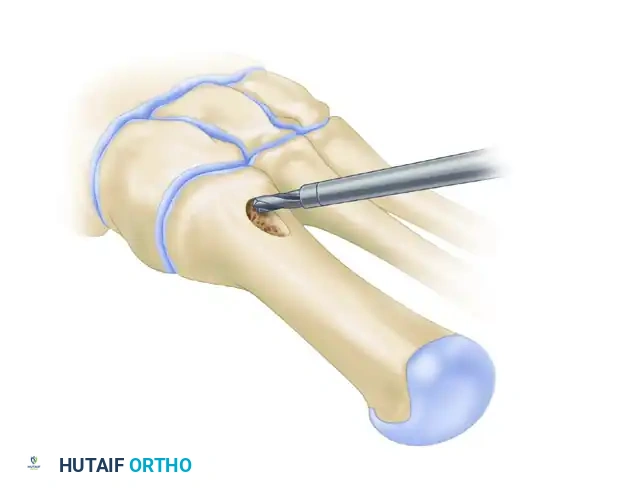

- Marking the Bone: Score the dorsal metatarsal transversely at two levels: 1 cm distal to the MTC joint (the osteotomy site) and 2 cm distal to the MTC joint (the screw fixation site).

- Pre-drilling the Glide Hole: Crucial Step. Drill a 3.5-mm glide hole at the 2-cm mark (1 cm distal to the planned osteotomy) in the center of the metatarsal shaft, directing it proximally. Performing this before the osteotomy ensures absolute stability during drilling.

- Executing the Osteotomy: Use a specialized curved crescentic saw blade. The convexity of the blade must face distally.

- Score the dorsal cortex, then gently rock the blade medially and laterally. Ensure the lateral aspect of the blade exits the lateral cortex cleanly. The medial cortex can be finished with a small osteotome if necessary.